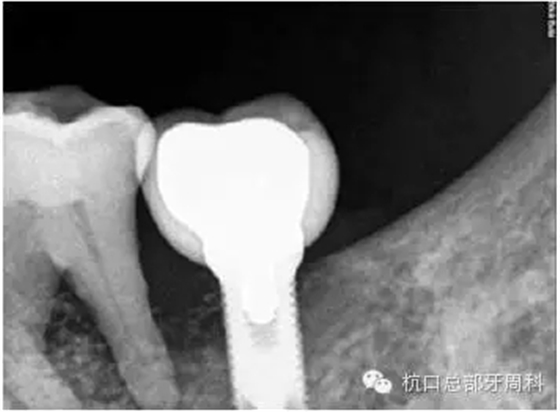

種植后即刻拍片 2005

被診斷為種周炎時全景片 2011

全景片:大范圍火山口樣/彈坑樣骨缺損

CT:左下缺牙區(qū)及部分升支存在骨破壞

初診時全景片2011.7